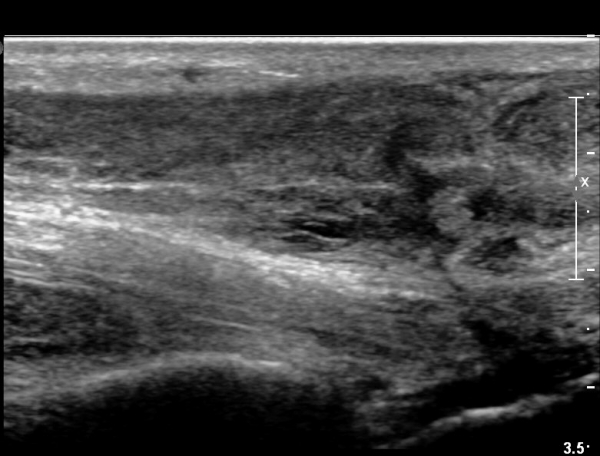

2018³â  1¿ù 30ÀÏ ÃßÀû°Ë»ç

¾ÆÅ³·¹½º°Ç Àú¿¡ÄÚºÎÁ¾ÀÌ °¨¼ÒµÇ°í  ÆÄ¿­ºÎÀ§ Àú¿¡ÄÚ°¡ È£ÀüµÇ¾î

°ÇÀÇ ¼¶À¯¼º¾ç»ó(fibrillar pattern)ÀÌ È¸º¹µÇ°í ±¹¼ÒÀû ¿¬°á¼º ¼Ò½ÇÀÌ »ç¶óÁü(»çÁø 9, 10, 11, 12).